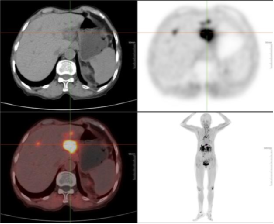

例一:患者53岁男性,肝内胆管癌术后7月余,八周期化疗后复查。图像第一排为FAPI显像;第二排为FDG显像。

肝顶部及残肝右叶病灶FDG显像未见明显显示,而FAPI显像明显显示,CT密度均未见明显异常。

且较本院增强MR及FDG显像新发现肝左叶病灶;右肺门淋巴结FDG显像及FAPI显像均代谢增高,高度怀疑转移灶。